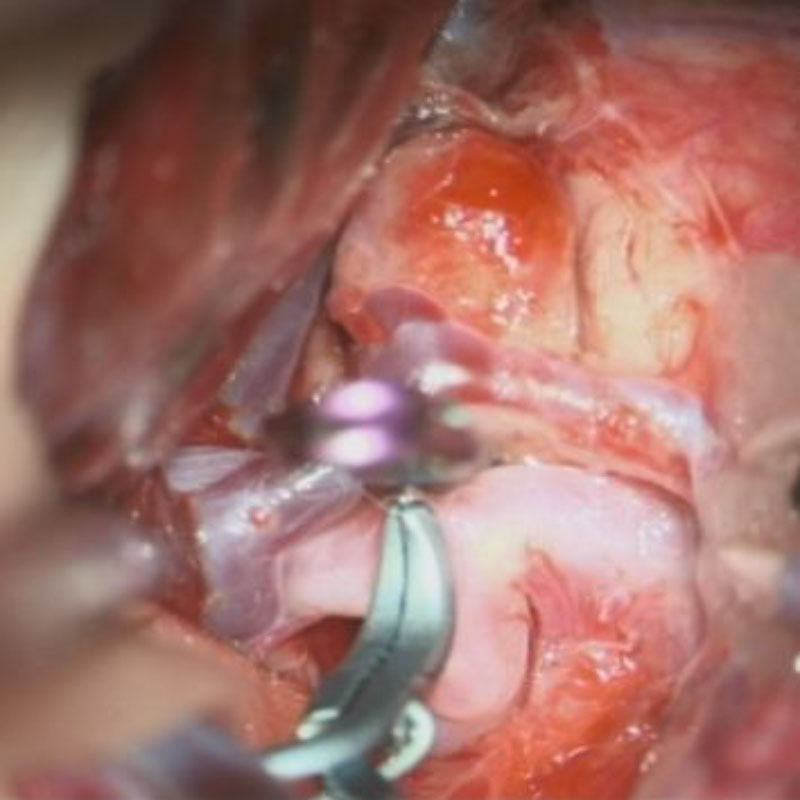

2

'26年1月

50代

右中大脳動脈瘤

クリッピング術

手術前

クリップ前

クリップ後

術後血管撮影